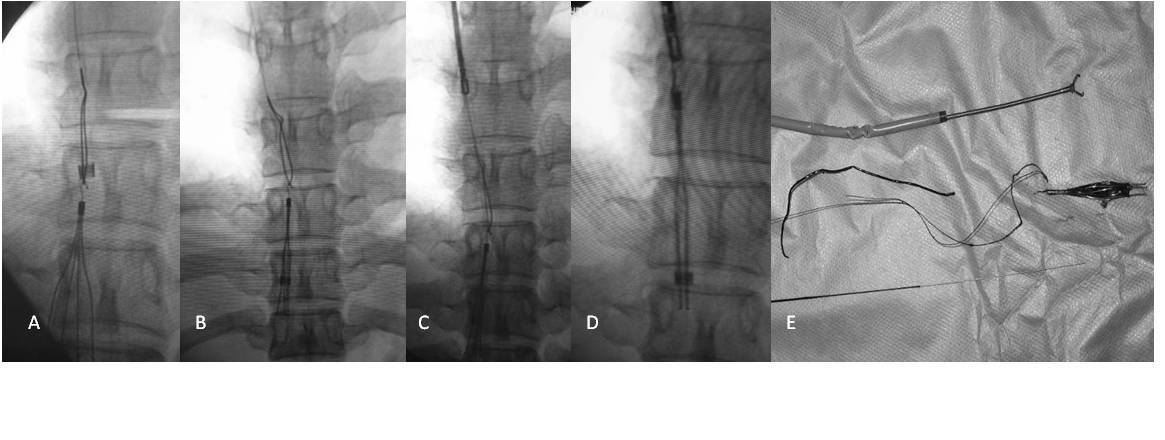

疑难性下腔静脉滤器取出的技巧及策略 - 好大夫

792x409 - 26KB - JPEG